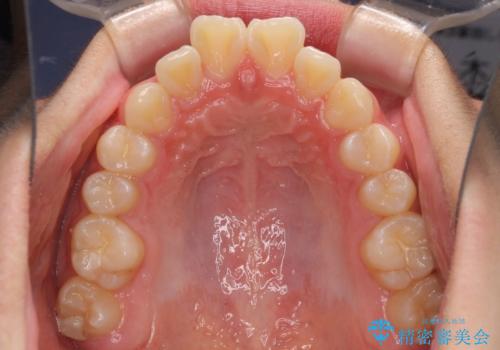

- 上下前歯のデコボコを改善したいとのことで来院された患者様です。

自己管理を減らしたいとのことで、ワイヤー装置による矯正治療を行うこととしました。

中学生と言うこともあり、1年強の短期間で終了しました。

歯磨きがしっかりとできないと虫歯になるリスクがありましたが、治療期間中は清潔な状態を保っていただけました。